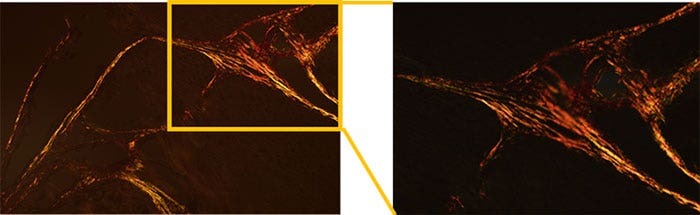

디밍을 사용하여 배경을 어둡게 한 편광 관찰

콜라겐 유형 I 및 III은 각기 주황색과 녹색으로 검출됩니다.

그림 2: 고광도 및 하이 컬러 렌더링 LED가 장착된 BX53 현미경